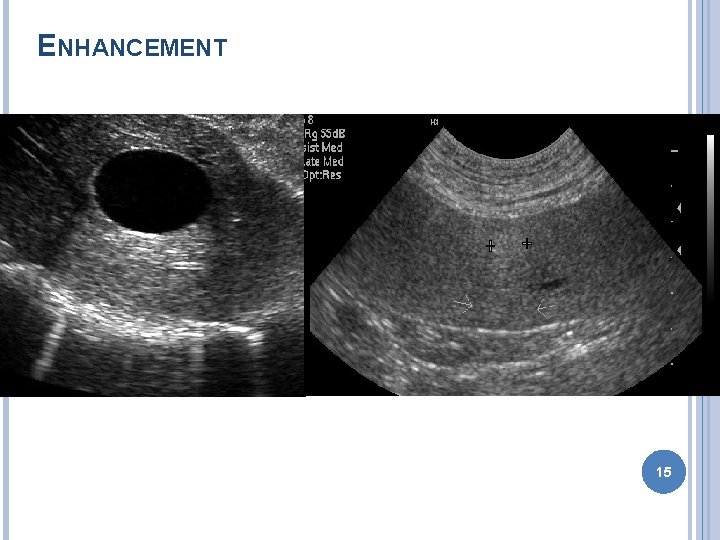

ARTIFACTS Improper machine settings – gain Reverberation � Mirror image – liver GB � Comet tail – gas bubble � Ring down – skin transducer surface Acoustic shadowing Acoustic enhancement Edge enhancement � Border of kidney 11

ENHANCEMENT 15